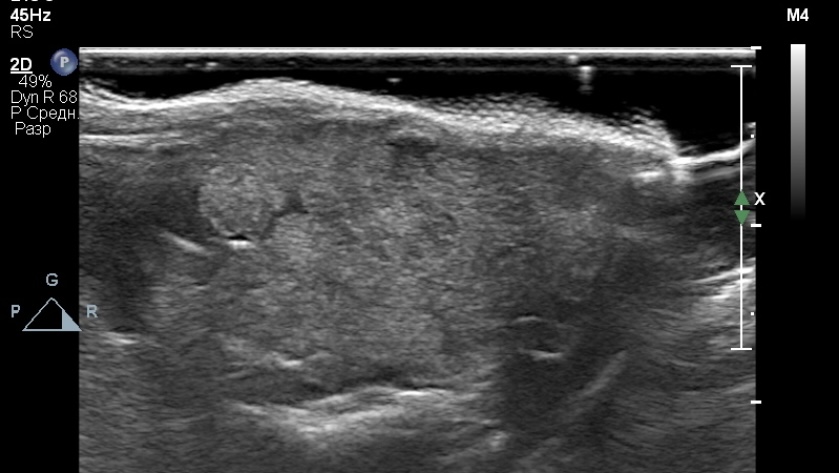

Животному были выполнены ультразвуковое исследование мягких тканей шеи, магнитно-резонансная томография области головы и шеи с контрастным усилением.Результаты УЗИ. В просвете ротоглотки было выявлено гетерогенное, преимущественно изоэхогенное образование с гипоэхогенными включениями неправильной формы, нечеткими контурами, размерами 15×16 мм (фото 2, 3).